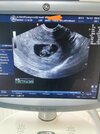

Mój bobo. Idealnie 8+1 :-) pięknie bije serduszko. Nie mogę powstrzymać łez :)

Załączniki

• 441a6530-ac08-4bd5-87dd-fef926782e70.jpg

441a6530-ac08-4bd5-87dd-fef926782e70.jpg

112,1 KB · Wyświetleń: 144